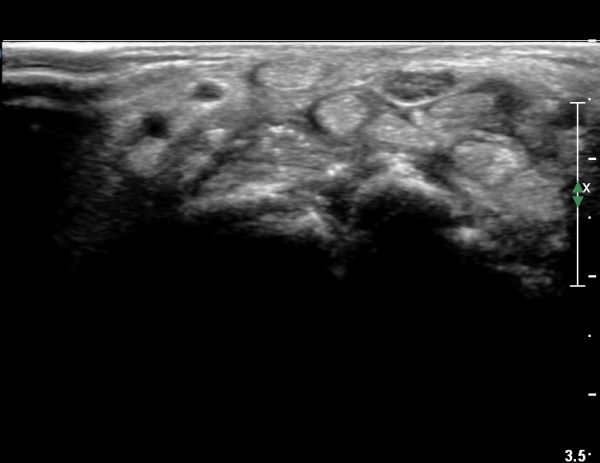

¼Õ¸ñ ºÎÀ§ Ⱦ´Ü¸é°Ë»ç¿¡¼ ¿ä°ñ°ú ¿ù»ó°ñ Àü¹æ¿¡ ¼®È¸È¼º À½¿µÀÌ Á¸ÀçÇϰí Àü¹ÝÀûÀÎ ¼öÁö ±¼°î°ÇÀÇ ºñÈÄ, Á¤Á߽ŰæÀÇ ºÎÁ¾°ú

ÈûÁÙ ¹× Á¤Á߽ŰæÀÇ Ç¥ÃþÀ¸·Î ÀüÀ§°¡ °üÂûµÈ´Ù, (»çÁø 1 ), ÆÄ¿öµµÇ÷¯°Ë»ç¿¡¼ Ç÷·ùÁõ°¡°¡ °üÂûµÊ´Ù(»çÁø 2)..